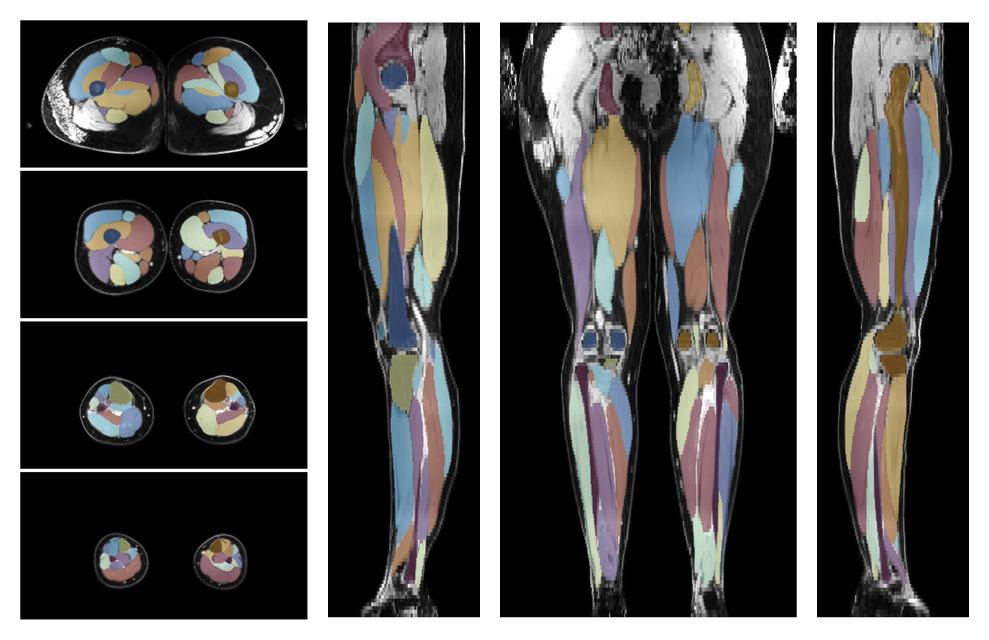

Muscle segmentation

Convolution neural network based (UNET) fiber automated muscle segmentation, for information look here».

• 3D volume render of automated muscle segmentation.

3D render of automated muscle segmentation labels generated using a CNN UNET.

• Automated muscle and bone segmentation.

Overlay of automated muscle segmentation labels on dixon water image.